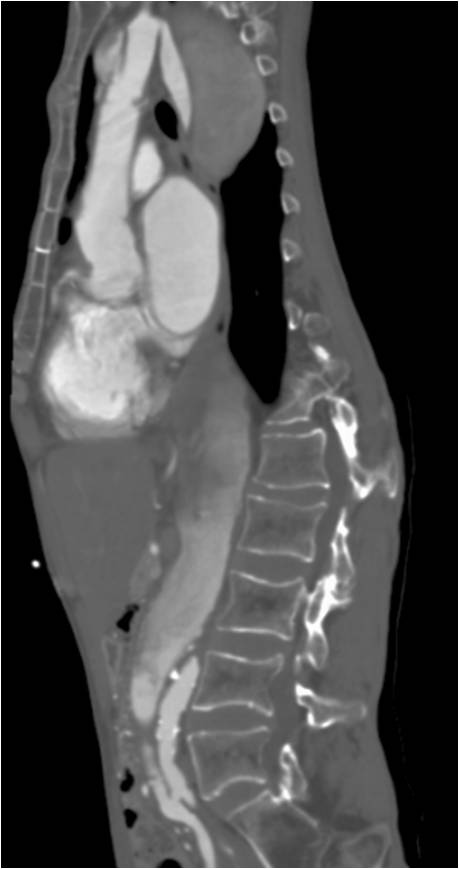

Pain and numbness of right lower limb (71 / M)

Ji Won Lee, Department of Radiology, Pusan National University Hospital

HIT : 23